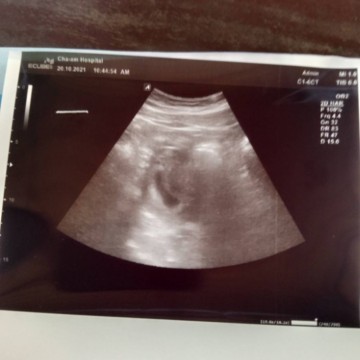

แม่ๆซาวด์เห็นตัวเด็กตอนกี่วีคบ้างคะ เราไปรอบแรกตอน6วีค ไม่เห็นอะไรเลย รอบล่าสุด9วีค ซาวด์เห็นแค่ถุงตามรูปเลยค่ะ เครียดมากเลยค่ะกลัวเป็นท้องลม #ซาวด์แค่หน้าท้องอย่างเดียวนะคะ

ใจเย็นค่ะ เราไปครั้งแรก นับจากปจด.จะได้ 7วีค แต่พอซาวด์เจอแต่ถุง หมอวัดถุงให้ก็ว่าน่าจะประมาณ 5วีค พออีกสองวีคเจอเด็ก 1.3ซ.ม.พร้อมเสียงหัวใจ อายุครรภ์ 7วีคค่ะ ดังนั้นซาวด์ครั้งที่สองเท่านั้นถึงจะมั่นใจได้ว่าท้องจริงหรือท้องลม ซาวด์ครั้งแรกอย่าเพิ่งเครียดไปค่ะ

แม่บ้านนี้ไปซาวด์รอบแรกคุณหมอบอกอายุครรภ์6สัปดาห์ เห็นแต่ถุงค่ะ (ซาวด์วันที่9ธ.ค) หมอนัดไปซาวด์ใหม่วันที่22ธ.ค อายุครรภ์8สัปดาห์2วันค่ะ เห็นเป็นตัวน้องแล้วค่ะ หัวใจเต้นแล้วด้วยค่ะ ยังไงคุณแม่อย่าเครียดไปนะคะท้องแต่ละคนไม่เหมือนกันค่ะ น้องอาจจะยังตัวเล็กอยู่เลยซาวด์ไม่เห็น รอหน่อยนะคะ เดี๋ยวก็เห็นตัวเล็กจ้า สู้ๆนะคะ

เราเองไปซาวครั้งแรกผ่านหน้าท้องไม่เจอน้องคะหมอบอกน่าจะท้องลม. เราเปลี่ยนหมอคะไปฝากคลีนิคถัดไปแค่วันเดียวซาวผ่านช่องคลอดเจอน้องพร้อมหัวใจเต้นแรงมากคะ. ของเราตอนนี้ตามใบซาวจะ8wคะ ใจเย้นๆนะคะทีแรกเราเครียดมากกัวท้องลม. หมอบอกถ้าซาวหน้าท้องจะไม่ค่อยเหนคะ

เหมือนกันเลยค่ะ เครียดมาก แต่เราซาวช่องคลอดแล้ววหมอบอกยังไม่เห็นตัวเด็ก แต่หมอบอกอีกอย่างค่ะว่า มันเรื่องปกติที่จะไม่เห็น เพราะถุงการตั้งครรภ์มันเล็ก แต่ถ้าถุงการตั้งครรภ์ใหญ่แล้ววยังไม่เห็นตัวเด็ก ก็แสดงว่าผิดปกติค่ะ